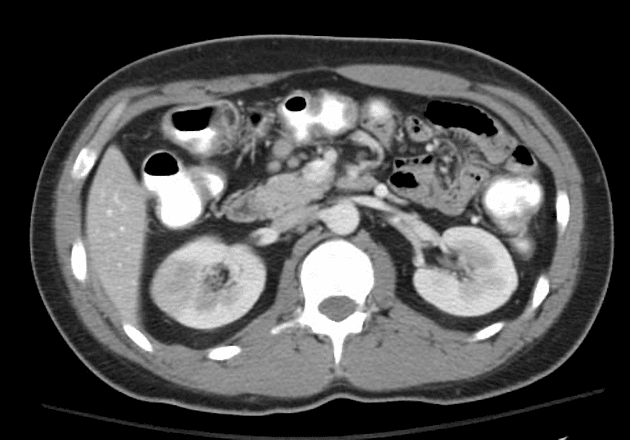

Axial low monoE

CT•Axial low monoE•1 / 175

- Lượng dịch tự do và khí trong ổ bụng nhiều, cho thấy thủng tạng rỗng (perforated hollow viscus). Phần lớn khí tự do nằm ở vùng trên bên phải ổ bụng.

- Các quai ruột non ở phía bên phải ổ bụng giãn vừa, nằm kề sát và trước đại tràng lên và manh tràng.

- Các quai ruột này cho thấy giảm rõ rệt tăng quang thành ruột (markedly reduced mural enhancement) (rõ nhất trên tái tạo low monoE), hình ảnh này gợi ý thiếu máu ruột (bowel ischemia).

- Động mạch mạc treo tràng trên (SMA), tĩnh mạch mạc treo tràng trên (SMV) và tĩnh mạch cửa (portal vein) thông thoáng (patent).

- Các nhánh động mạch mạc treo tràng trên cung cấp máu cho vùng này được cản quang kém.

- Dựa vào phân bố các quai ruột bị tổn thương, thoát vị nội tạng (internal hernia) được nghi ngờ.

- Có bằng chứng của thủng tạng rỗng (perforated hollow viscus), nguồn gốc có khả năng nhất là các quai ruột ở vùng bụng phải trước có hình ảnh thiếu máu (ischemic). Nguyên nhân cơ bản chưa rõ, thoát vị nội tạng (internal hernia) là một khả năng (qua mạc treo – trans mesenteric).